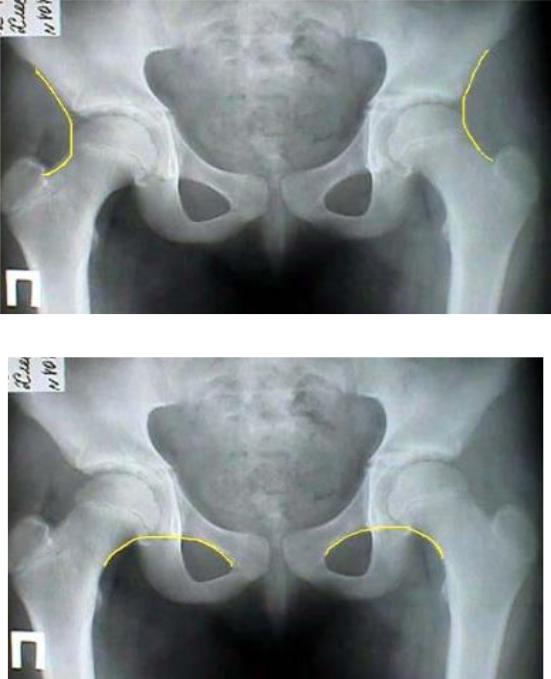

Схема Кальве. Линия Кальве - линия, соединяющая наружный край подвздошной кости и верхний край шейки бедра (рис. 74).

В норме образует правильную непрерывную дугообразную линию.

При подвывихе или вывихе в т/б суставе линия становится прерывной,

неправильной.

Схема Шентона. Линия Шентона - линия, соединяющая нижний край шейки бедра и верхний край запирательного отверстия (Рис. 75). В норме образуется ровная дугообразная линия. При подвывихе и вывихе - шейка бедра смещается кверху, дугообразная линия прерывается.

Рис. 74. Схема Кальве

Рис. 75. Схема Шентона